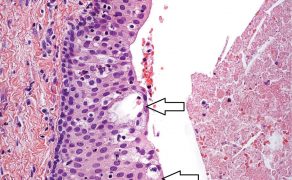

Adhezyjna odbudowa zębów trzonowych po leczeniu endodontycznym przy pomocy endokoron – opis przypadków

TITLE: Adhesive restoration of endodontically treated molars with endocrowns – a case report

STRESZCZENIE: Odbudowa zębów po leczeniu endodontycznym jest kluczowa w celu jak najdłuższego ich zachowania. Według badań nieszczelna rekonstrukcja jest najczęstszą przyczyną utraty zębów leczonych endodontycznie. Ciągły rozwój stomatologii pozwala na oszczędniejsze opracowanie takich zębów pod przyszłe odbudowy protetyczne cementowane adhezyjnie. W artykule tym przedstawiono przypadki rekonstrukcji zębów trzonowych leczonych endodontycznie przy pomocy endokoron.

SUMMARY: Restoration of endodontically treated teeth is crucial in order to preserve them as long as possible. According to research, leaky reconstruction is the most common cause of loss of endodontically treated teeth. The continuous development of dentistry allows for minimally invasive instrumentation of such teeth for future adhesively cemented prosthodontic restorations. This article presents cases of endodontically treated molars reconstructed with endocrowns.

Zęby leczone endodontycznie w większości przypadków wymagają odbudowy protetycznej.

Zwykle w takich zębach występuje duża utrata ich tkanek twardych, spowodowana przez wcześniejsze znaczne ubytki próchnicowe.